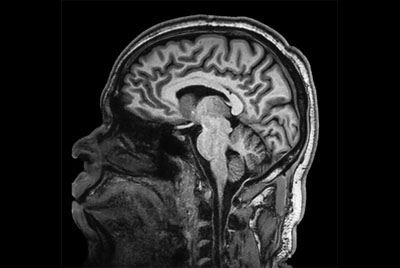

Brain overview

Comprehensive Brain imaging at 1.5T

Comprehensive Brain imaging at 3.0T